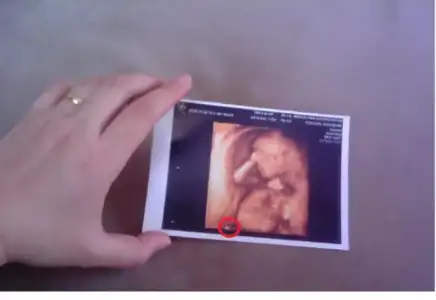

Doktordan geldim şimdi, yine çiklata yedim gittim ama bizim sıpa bugün uyuyordu, sonra uyandı, bissürü pozlar verdi bize

Doktor maşallah 2 gün de önden gidiyor bebiş dedi

Yanlız pek bir edepsiz, yiğidin malı meydanda misali her şey apaçık ortadaydı

Bu sefer resim şeklinde verdi, hemen astım dolabın üstüne, gülme sebebim, canım bebeğim seni çok seviyorum....

Doktordan geldim şimdi, yine çiklata yedim gittim ama bizim sıpa bugün uyuyordu, sonra uyandı, bissürü pozlar verdi bize

Doktor maşallah 2 gün de önden gidiyor bebiş dedi

Yanlız pek bir edepsiz, yiğidin malı meydanda misali her şey apaçık ortadaydı

Bu sefer resim şeklinde verdi, hemen astım dolabın üstüne, gülme sebebim, canım bebeğim seni çok seviyorum....

Doktordan geldim şimdi, yine çiklata yedim gittim ama bizim sıpa bugün uyuyordu, sonra uyandı, bissürü pozlar verdi bize

Doktor maşallah 2 gün de önden gidiyor bebiş dedi

Yanlız pek bir edepsiz, yiğidin malı meydanda misali her şey apaçık ortadaydı

Bu sefer resim şeklinde verdi, hemen astım dolabın üstüne, gülme sebebim, canım bebeğim seni çok seviyorum....